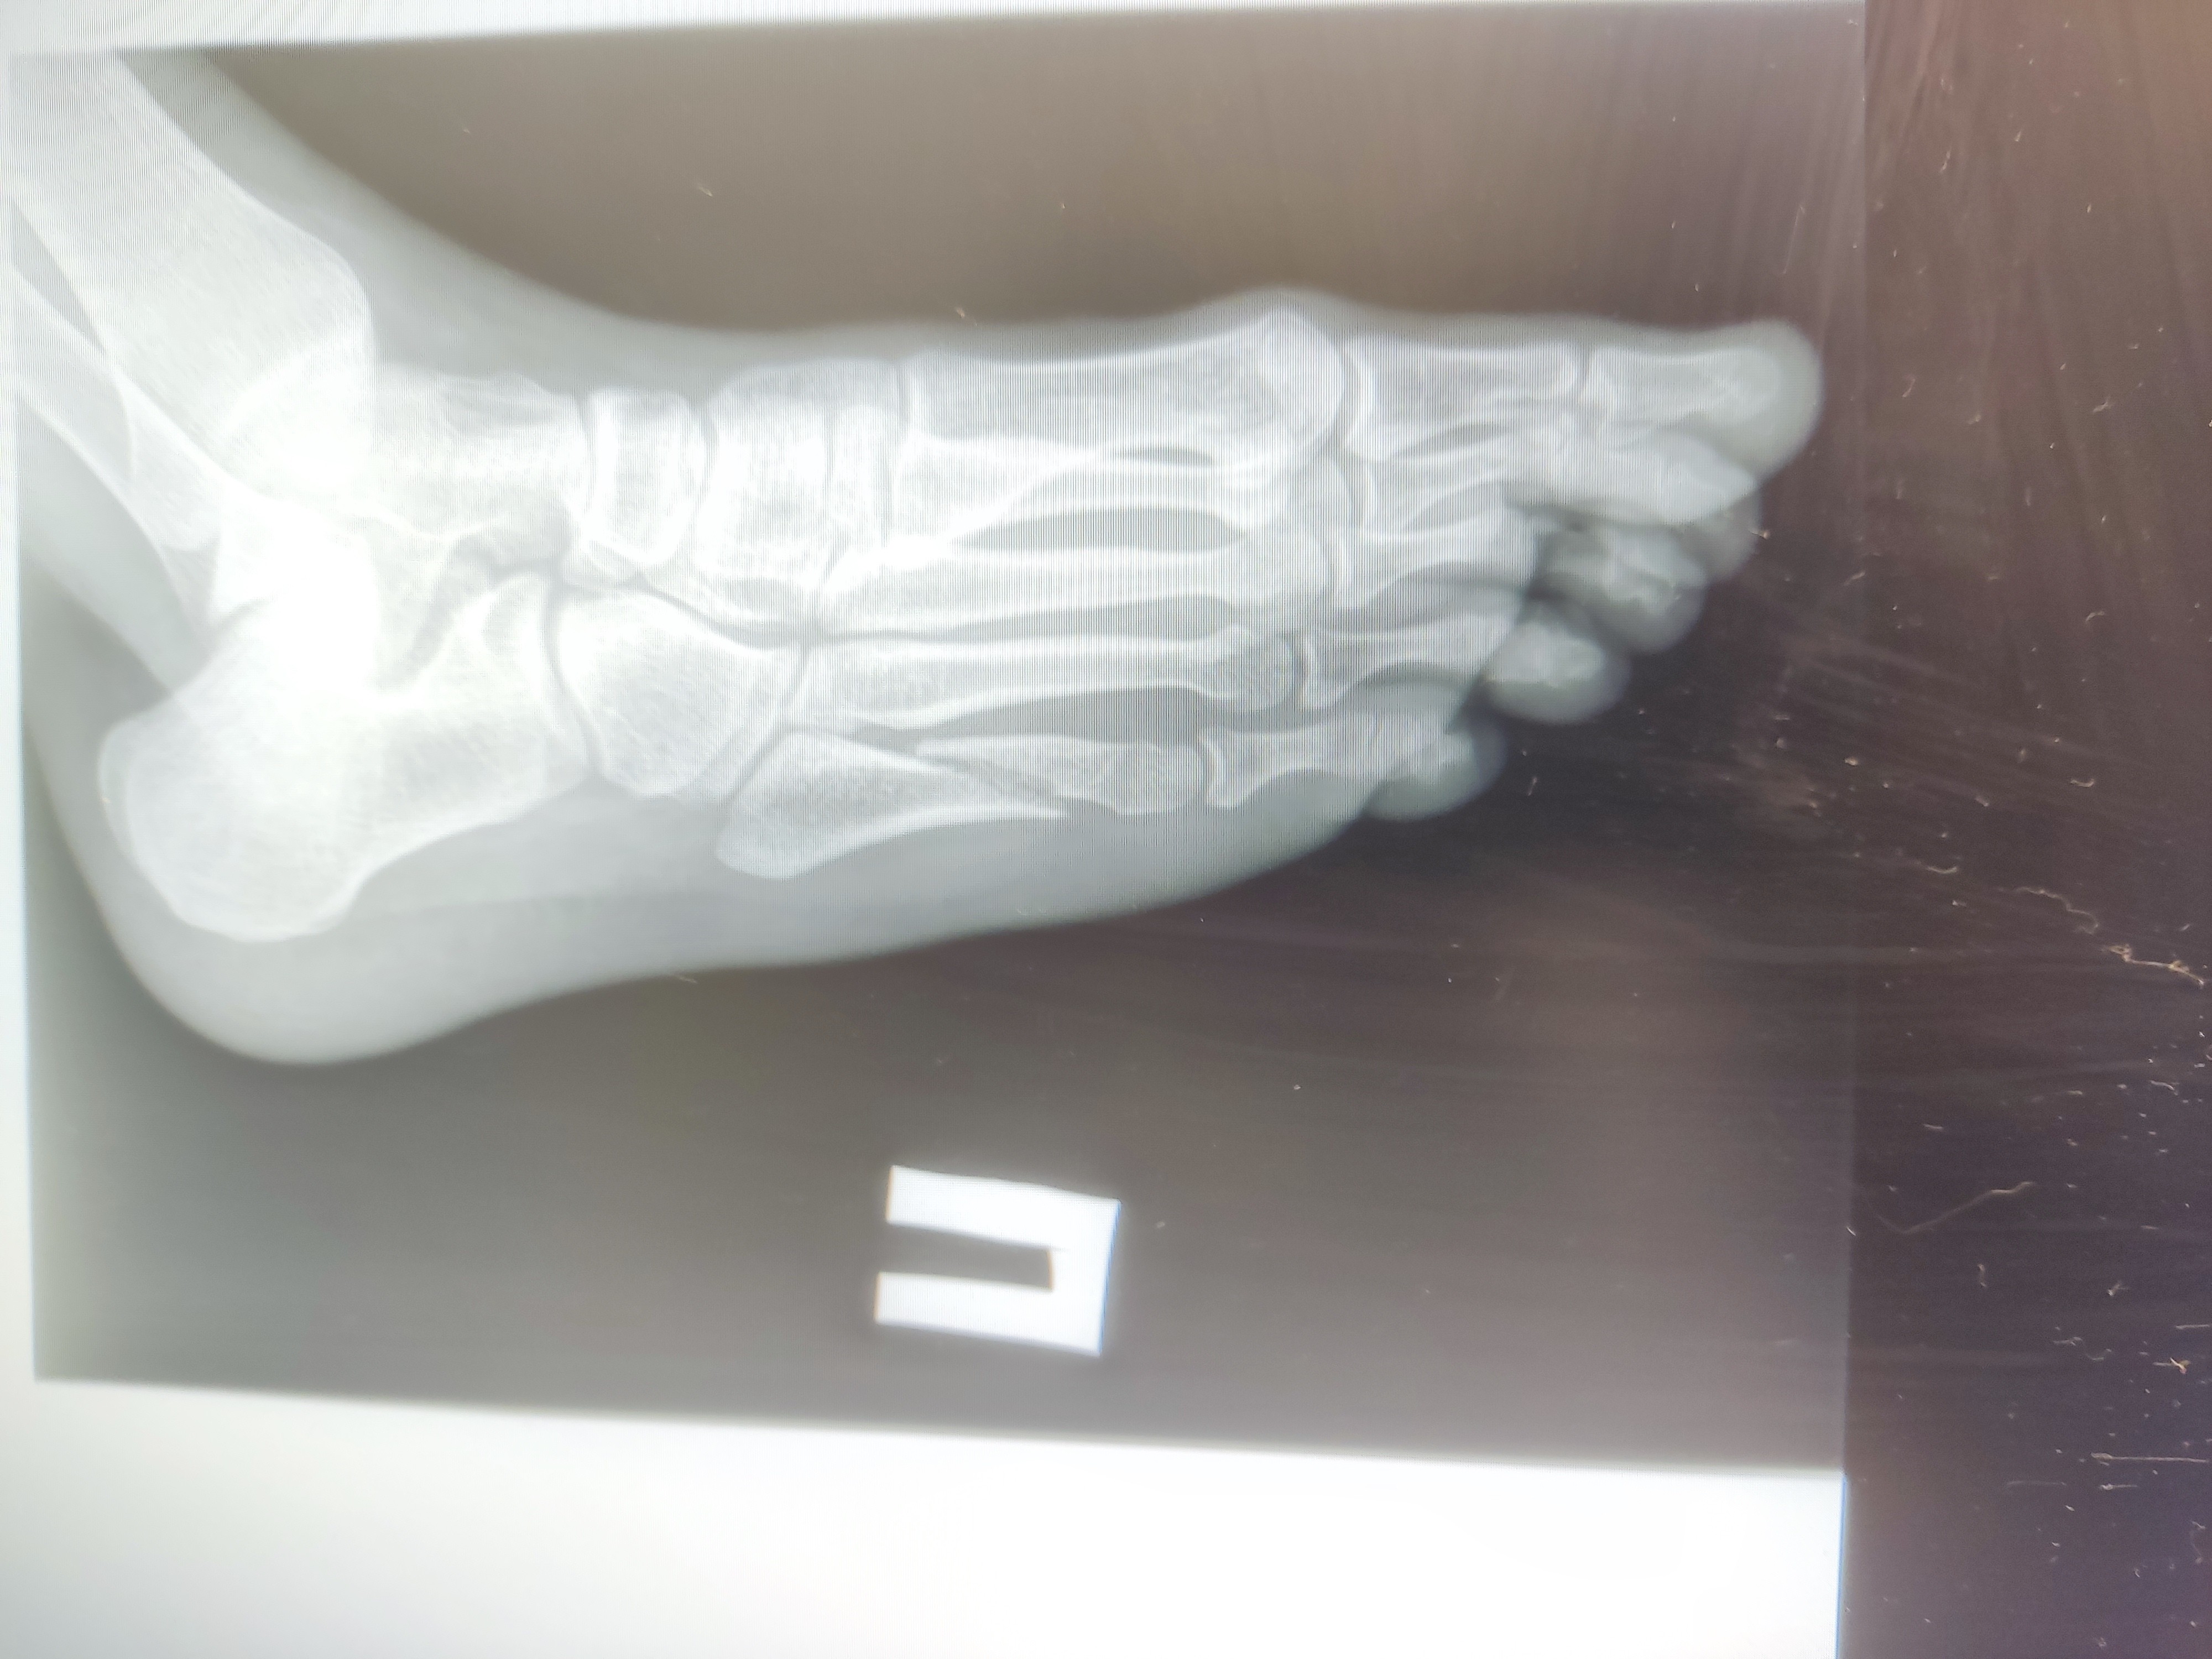

Салют, поперечное плоскостопие + 1 ст. Артроза большого пальчика)

Вкатываюсь одной ногой в тред вместе со своим заболеванием.

Подскажите, как живете с ним? Хирург был старый пердун и прописал просто Стельки, супинаторы, самомассаж)) Скоро пойду к другому.

Как живете с такой же хуйней? Какую обувь носите? Какие стельки можете посоветовать, если живете в ДС. Как полет?

Коротко о себе: весил всю жизнь не больше 75. Бухал категорически мало, занимался переодически спортом, любил вот бегать. 32 лвл.

>>1638198

Стельки делай индивидуальные. Footmaster, Formthotics, Сурсил-орто

Да любые почти, чтобы точно под твою ногу.